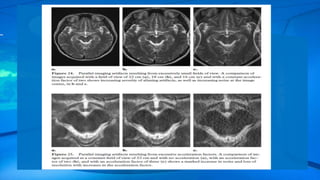

Parallel Imaging Artifact

New signal acquisition schemes such as SMASH (simultaneous acquisition of spatial harmonics),

• 56.

Parallel Imaging Artifact Newsignal acquisition schemes such as SMASH (simultaneous acquisition of spatial harmonics), SENSE (sensitivity encoding), and GRAPPA (generalized auto calibrating partially parallel acquisitions), which are categorized as parallel imaging techniques, have spawned a whole new avenue for growth in MR imaging methods and applications.